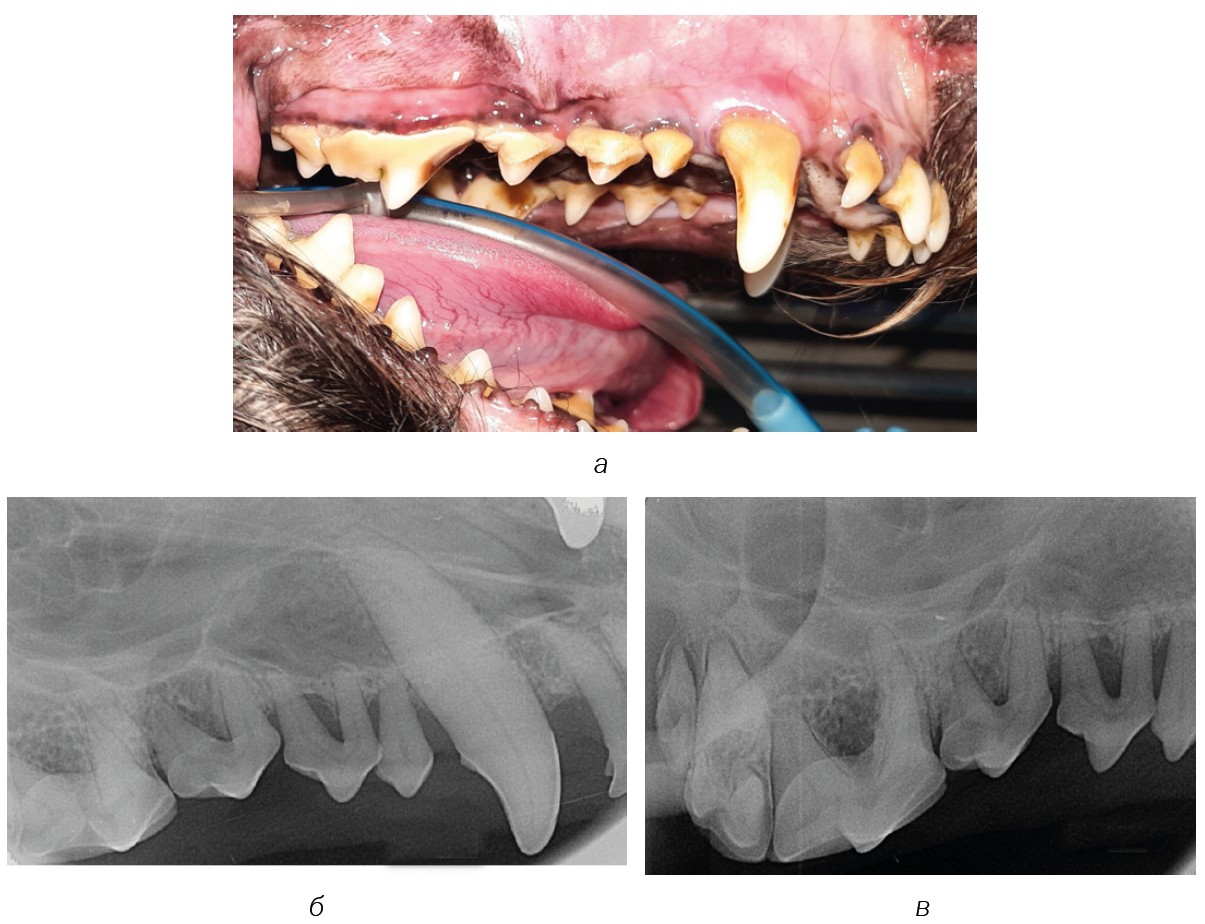

Fig. 8. Dental calculus stage 3: а — quadrant 100; б and в — Intraoral radiograph for stage 3 dental calculus

Source: VTC "Dentalvet".